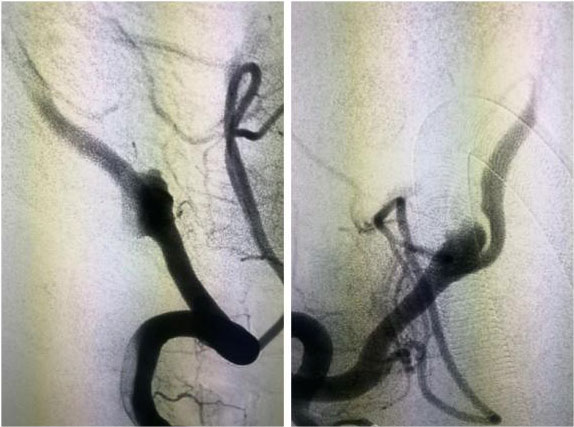

▲ 一位动脉瘤患者术前影像

▲ 术后,造影显示动脉瘤无显影,栓塞成功